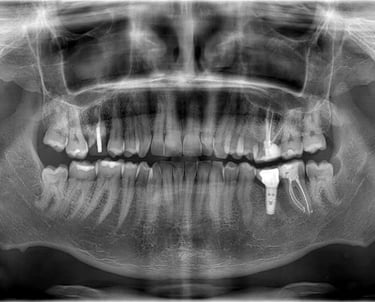

Ортопантомографията или т. нар. Панорамна снимка (зъбни снимки или снимки на зъби) показва общ изглед на съзъбието, челюстите, максиларните синуси и темпоромандибуларните стави. Изследването е стандарт в ежедневна практика на денталния лекар при сваляне на зъбния статус и прилежащите твърди тъкани, за контрол преди и след проведено дентално лечение. Чрез нея се откриват вродени аномалии, патологични процеси, фрактури, кисти и положението им спрямо костта, състоянието на алвеоларния гребен, съотношението между синусния контур и апексите на зъбите, използва се за визуализация на зъбни зародиши при ортодонтско лечение и др.